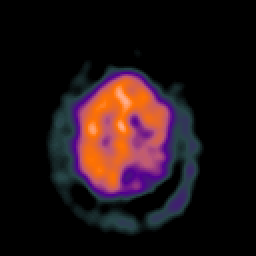

SPECT TC Study #2 -- Slice #43

[Home][Help][Clinical][Tour 1][Tour 2][Tour 3] Slice 43